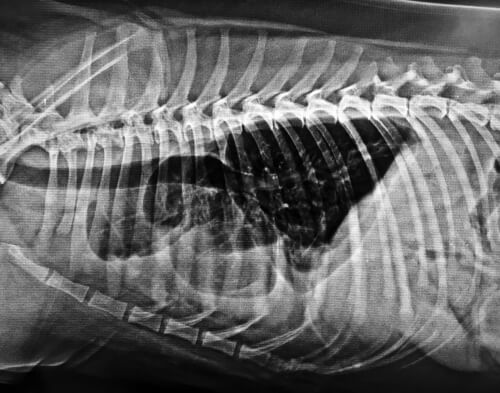

Se ha demostrado que los niveles de CoQ10 están reducidos en los corazones de las mascotas con enfermedades cardíacas. En consonancia, el uso más frecuente de CoQ10 en perros es como coadyuvante en el tratamiento de la insuficiencia cardíaca congestiva.

La coenzima Q10 es efectiva en el tratamiento de la miocardiopatía canina y enfermedades relacionadas.